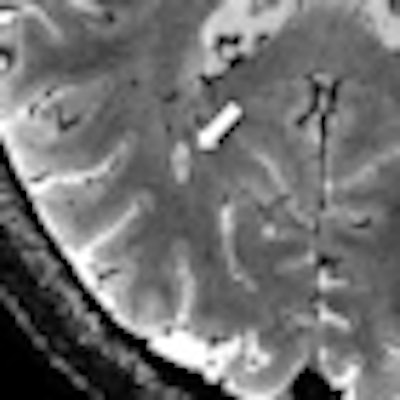

Specifically, deoxygenated blood in veins has different magnetic properties than oxygenated blood in arteries. Using a 7-tesla MRI technique known as T2*-weighted imaging, researchers can make veins appear especially dark, while MS lesions look bright. "Previously, it has not been possible to see this in live patients using a single brain scan," Mistry added. "Now, with T2* MRI, we can."

Using the 7-tesla MRI technique, 20 (80%) of the 25 patients could be diagnosed. Thirteen patients were diagnosed with MS; all of these patients had central veins visible in more than 40% of brain lesions. The seven patients with an eventual non-MS diagnosis had central veins visible in less than 40% of brain lesions.

| Using 7-tesla and 3-tesla T2*-weighted MRI, multiple sclerosis lesions characteristically had appearances reminiscent of a donut or coffee bean. Using guidelines based on counting a few of these characteristic lesions, the diagnosis could be correctly identified. Images courtesy of Dr. Niraj Mistry. |